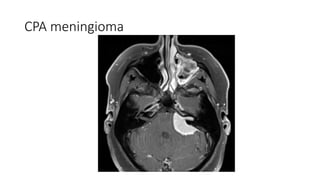

CPA meningioma

Location Supratentorial (90%) Parasagital region(falx)and cerebral convexities( 45%) Sphenoid ridge(15-20%) Olfactory grove(5-10%) Parasellar (5-10%) Other(5%): intraventricular, optic nerve sheath, pineal region  Infratentorial (8-10%) Cerebellopontine angle, clivus Multiple meningioma in1-9% cases

Differtiating points Suprasellarmeninigioma Papillary Craniophayngioma Chaismatic Hypothalamic glioma Definition A tumour originating from arachnoid cell rest(which are related to dura mater arachnoid granulations) A benign mostly solid suprasellar tumor arising from squamous epithelial remnants of rathke’s pouch An astrocytic tumor Age Middle decades Middle decades Usually 4rth to 6th decade Childhood Location and extention Tebercular , dorsal or diapgragm sellae Often shows forward extension along dura mater of anterior cranial fossa Commonly located within the suprasellar region A purely intrasellar location is uncommon optic chiasm and optic tract. Chaismal tumor tumors may into hypothalamus

Differentiatig points Suprasellarmeningioma Papiilary Craniopharyngioma Chiasmatic Hypothamic glioma NECT Usullally broad dural based, hyperdense lesion Calcification is seen 20% cases Usuully solid suprasellar tumour Small cysts but not a significant feature calcification is absent Often large and lobulated when at chiasm and can extend into hypothalamus No calcification CECT/MRC+ Avidly homogenous enhancement Soild component-intense contrast inhencement Variable inhancement T2WI Frequently isointense to cortex High signal intesity High signal intensity Bony hyperostosis Usually present Absent Absent Dural tail sign Usually present Absent Absent